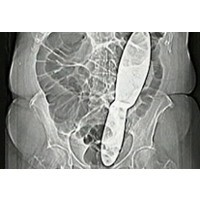

Alat Bedah Tertinggal di Perut Pasien - detikHealth Rabu, 17 Feb 2010 14:15 WIB Praha - (ir/ver) Infografis Lainnya Infografis Feeding Difficulty Vs Picky Eating, Apa Beda & Dampaknya bagi BB Anak? Infografis Waspadai Dampak Picky Eating pada Anak, Berikut Cara Jitu Cegahnya Infografis Infografis: Strategi dan Formasi Ideal untuk Menang Lomba Balap Bakiak